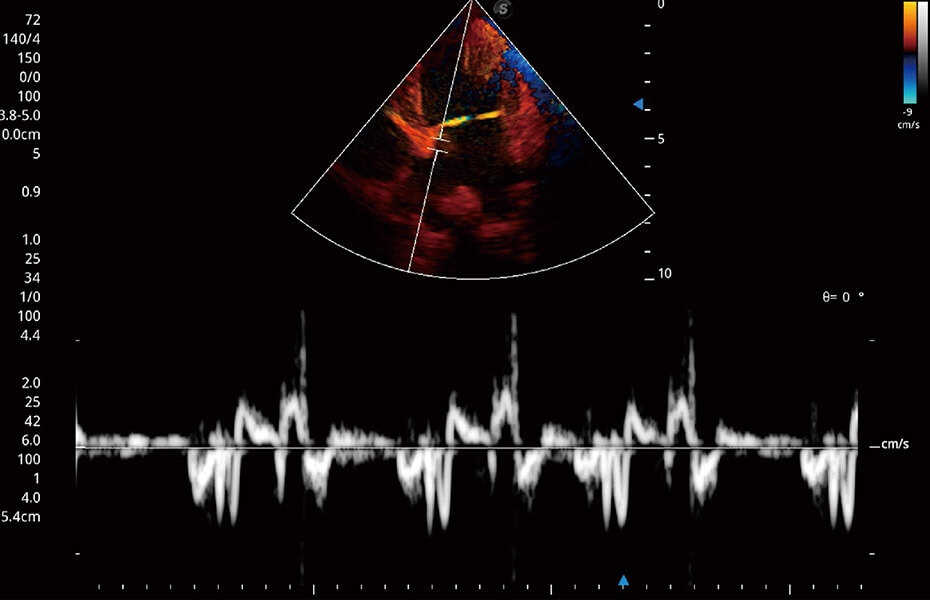

(貓)髂動(dòng)脈血流頻譜

(犬)心臟組織多普勒